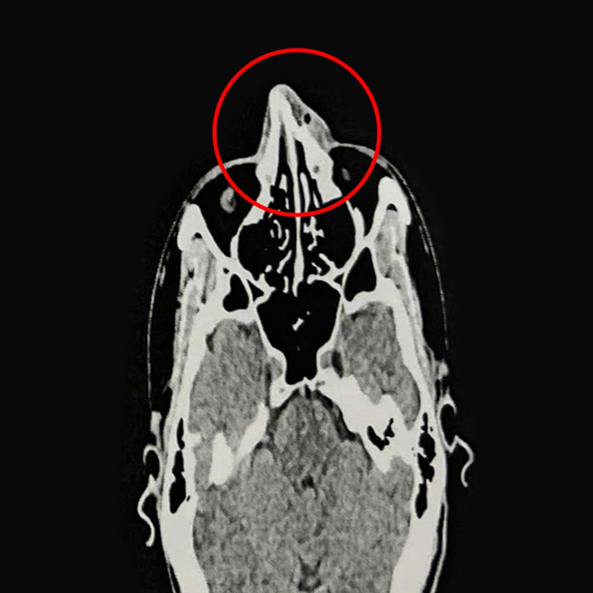

ThS.BS.CKI Nguyễn Trung Nguyên, Trung tâm Tai Mũi Họng, Bệnh viện Đa khoa Tâm Anh TP.HCM, cho biết kết quả nội soi và chụp CT 128 lát cắt ghi nhận xương mũi của anh Phi bị gãy ở vị trí tháp mũi, phù nề tụ khí mô mềm vùng mũi, lệch vách ngăn mũi, viêm mũi xuất tiết. Anh Phi được chỉ định phẫu thuật nâng xương mũi, chỉnh hình vách ngăn mũi.

Người đàn ông TP.HCM gãy xương mũi vì chơi Pickleball- Ảnh 1.